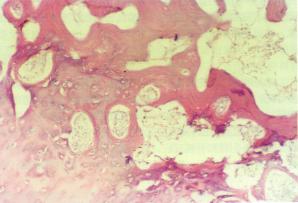

外科感染---遷延1、局限化、吸收或形成膿腫當人體抵抗力占優勢,感染便局限化,有的自行吸收,有的形成膿腫。而小的膿腫也可自行吸收;較大膿腫在破潰或經手術切開排膿後,轉為修復過程,病變區逐漸長出肉芽組織,形成瘢痕而愈。